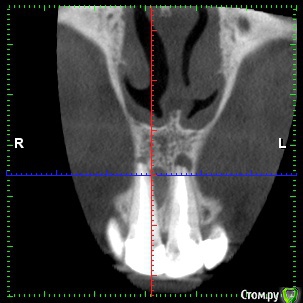

dentikl Опубликовано 22 декабря, 2016 Автор Поделиться Опубликовано 22 декабря, 2016 Потому что дефект 3-х стеночный и не выходит за границы контура челюсти,об'ем конечно кости уменьшаетсявот этот случай требует мембраны и индуктора?Ретроградно пломбировать даже если пройду на ревизии? Ссылка на комментарий

Доктор Добрых Дел Опубликовано 22 декабря, 2016 Поделиться Опубликовано 22 декабря, 2016 В области 11 случайно не трещина корня? Медиально очаг деструкции как-то намекает на это 1 Ссылка на комментарий

Тимур86 Опубликовано 22 декабря, 2016 Поделиться Опубликовано 22 декабря, 2016 киста сбоку говорит о том что в корне скорее всего трещина Ссылка на комментарий

Bier Опубликовано 22 декабря, 2016 Поделиться Опубликовано 22 декабря, 2016 не трещина там, а латераль скорее всего. Так высоко корень только от удара может сломаться. dentikl методика РВК применяется только при невозможности или безуспешности ортоградного лечения. Т.е. в вашем случае оперировать не нужно, нужно ждать излечения. Если же вы проводите РВК - единственным смыслом этой операции является установка апикальной пломбы, желательно не короче 3-4мм вглубь канала. Прорут, Триоксидент, IRM, или биокерамика - подходят для этих целей. 4 Ссылка на комментарий

dentikl Опубликовано 3 января, 2017 Автор Поделиться Опубликовано 3 января, 2017 В области 11 случайно не трещина корня? Медиально очаг деструкции как-то намекает на этоВы правы.Там таки была перфа не середине мщ поверхности корня.Кисту извлекли,перф прикрыли,жду. Ссылка на комментарий

dentikl Опубликовано 3 января, 2017 Автор Поделиться Опубликовано 3 января, 2017 киста сбоку говорит о том что в корне скорее всего трещинаДа,там была перфа,Вы-правы. Ссылка на комментарий